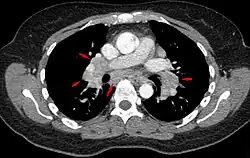

Da potenziell jedes Organ durch die Krankheit betroffen sein kann, richtet sich die Diagnostik nach der jeweiligen Beschwerdesymptomatik. Aufgrund der oft symptomlos verlaufenden Lymphknotenschwellungen wird die Sarkoidose nicht selten zufällig beim Röntgen-Thorax festgestellt. Je nach Befallsmuster und Zeichnung im Röntgenbild oder in der Computertomographie kann die pulmonale Sarkoidose in folgende Stadien (nach Scadding, 1961[15]) eingeteilt werden, wobei diese Einteilung oft die Schwere und die Prognose der Erkrankung nicht wiedergibt:[16]

- Stadium 0: Normalbefund der Lunge bei Befall eines anderen Organs

- Stadium I: symmetrische Lymphknotenvergrößerung ohne sichtbaren Befall des Lungengewebes

- Stadium II: beidseitige Lymphknotenvergrößerung mit perilymphatischer Bildung von Granulomen im Lungengewebe

- Stadium III: Lungenbefall mit fehlender Lymphknotenvergrößerung

- Stadium IV: fibrotischer Umbau des Lungengewebes mit Funktionsverlust der Lunge.

Eine Lungenfunktionsprüfung, meist auch eine Röntgenaufnahme der Lunge sowie eine Computertomographie werden durchgeführt, um die Therapiebedürftigkeit abschätzen zu können. Eine bronchoalveoläre Lavage (BAL) mit Zytologie kann oft diagnoseweisend sein. Sie zeigt typischerweise eine lymphozytäre Alveolitis mit Zunahme des CD4/CD8-Quotienten durch Erhöhung der Zahl der T-Helferzellen. Der Quotient beträgt beim Gesunden ca. 2, bei akuter Sarkoidose > 5. Eine transbronchiale Lungenbiopsie oder durch endobronchialen Ultraschall (EBUS) gezielte transbronchiale Biopsie der vergrößerten mediastinalen Lymphknoten kann histopathologisch zur Diagnosesicherung beitragen. Dabei werden in den Präparaten insbesondere nicht-verkäsende, epitheloidzellige Granulome mit Langhansschen Riesenzellen und einem Randwall aus Lymphozyten, Monozyten und Fibroblasten beobachtet. Das histologische Bild ist allerdings nicht spezifisch für die Sarkoidose. Die früher durchgeführte 67Ga-Szintigrafie wurde durch die FDG-PET/CT-Untersuchung abgelöst. Sie dient einerseits zur Kontrolle der Effektivität der durchgeführten Therapie, andererseits kann mit einer Untersuchung ein Überblick über die Anzahl der betroffenen Organsysteme gewonnen werden.